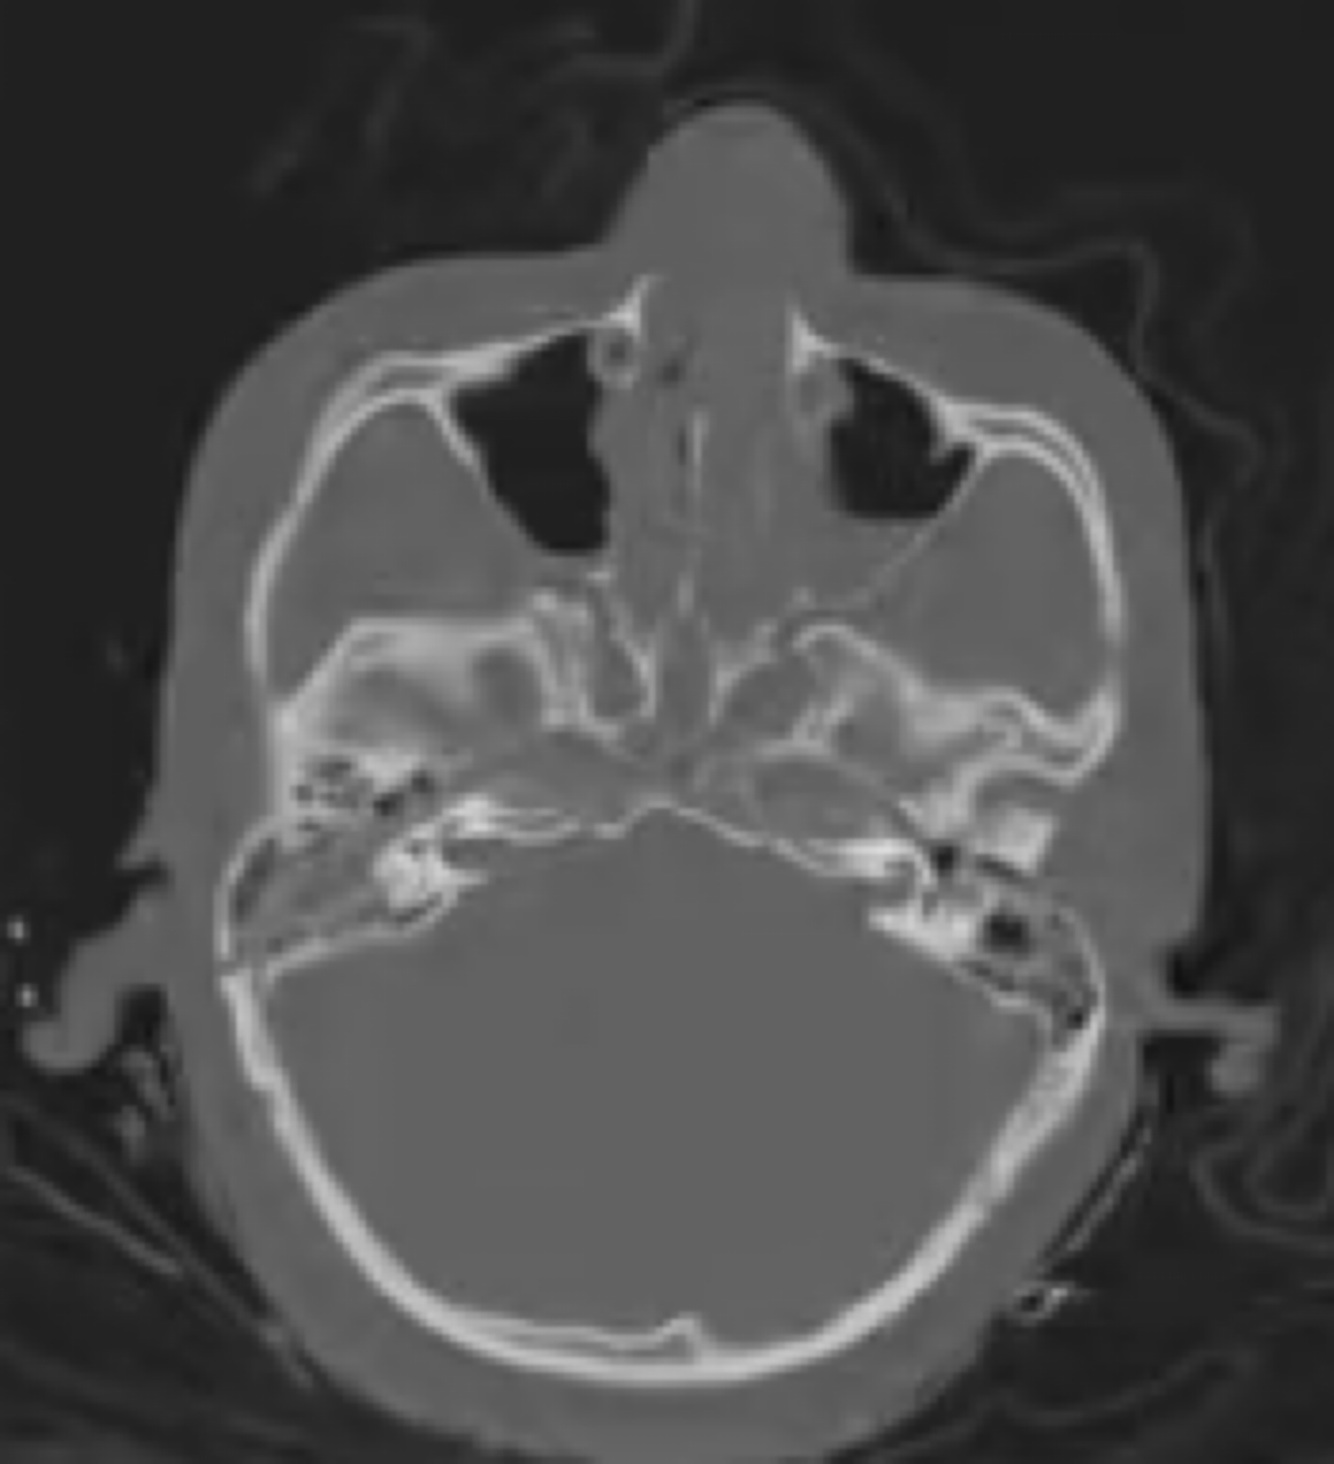

Tipo de fratura a seguir:

A

Linear.